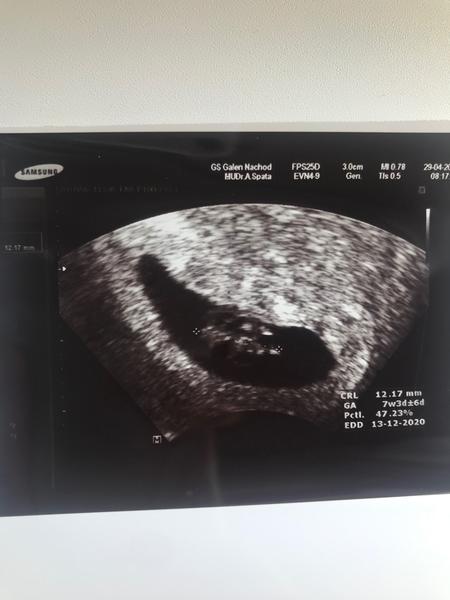

Co kde miminko na fotce z ultrazvuku má. Poznáte to některá?

@andyskarsgard já jsem byla asi v 7 týdnu. Takže tady na té fotce to vypadá jako flek. Ale v reálu bylo miminko hezčí. Ale aspoň, že jsem slyšela srdíčko. 😊

Takhle brzy fakt nic moc nepoznáš... je tam akorát změřená délka plodu... od křížku ke křížku, to je dole i apsané... kolik má mm, jinak by tam mohlo být vidět srdíčko, ale který z těch tmavších flíčk to je nepoznám, určitě bylo při ultrazvuku vidět jak tam tepe. ( na té první větší kontrole už to bude vidět pěkně )